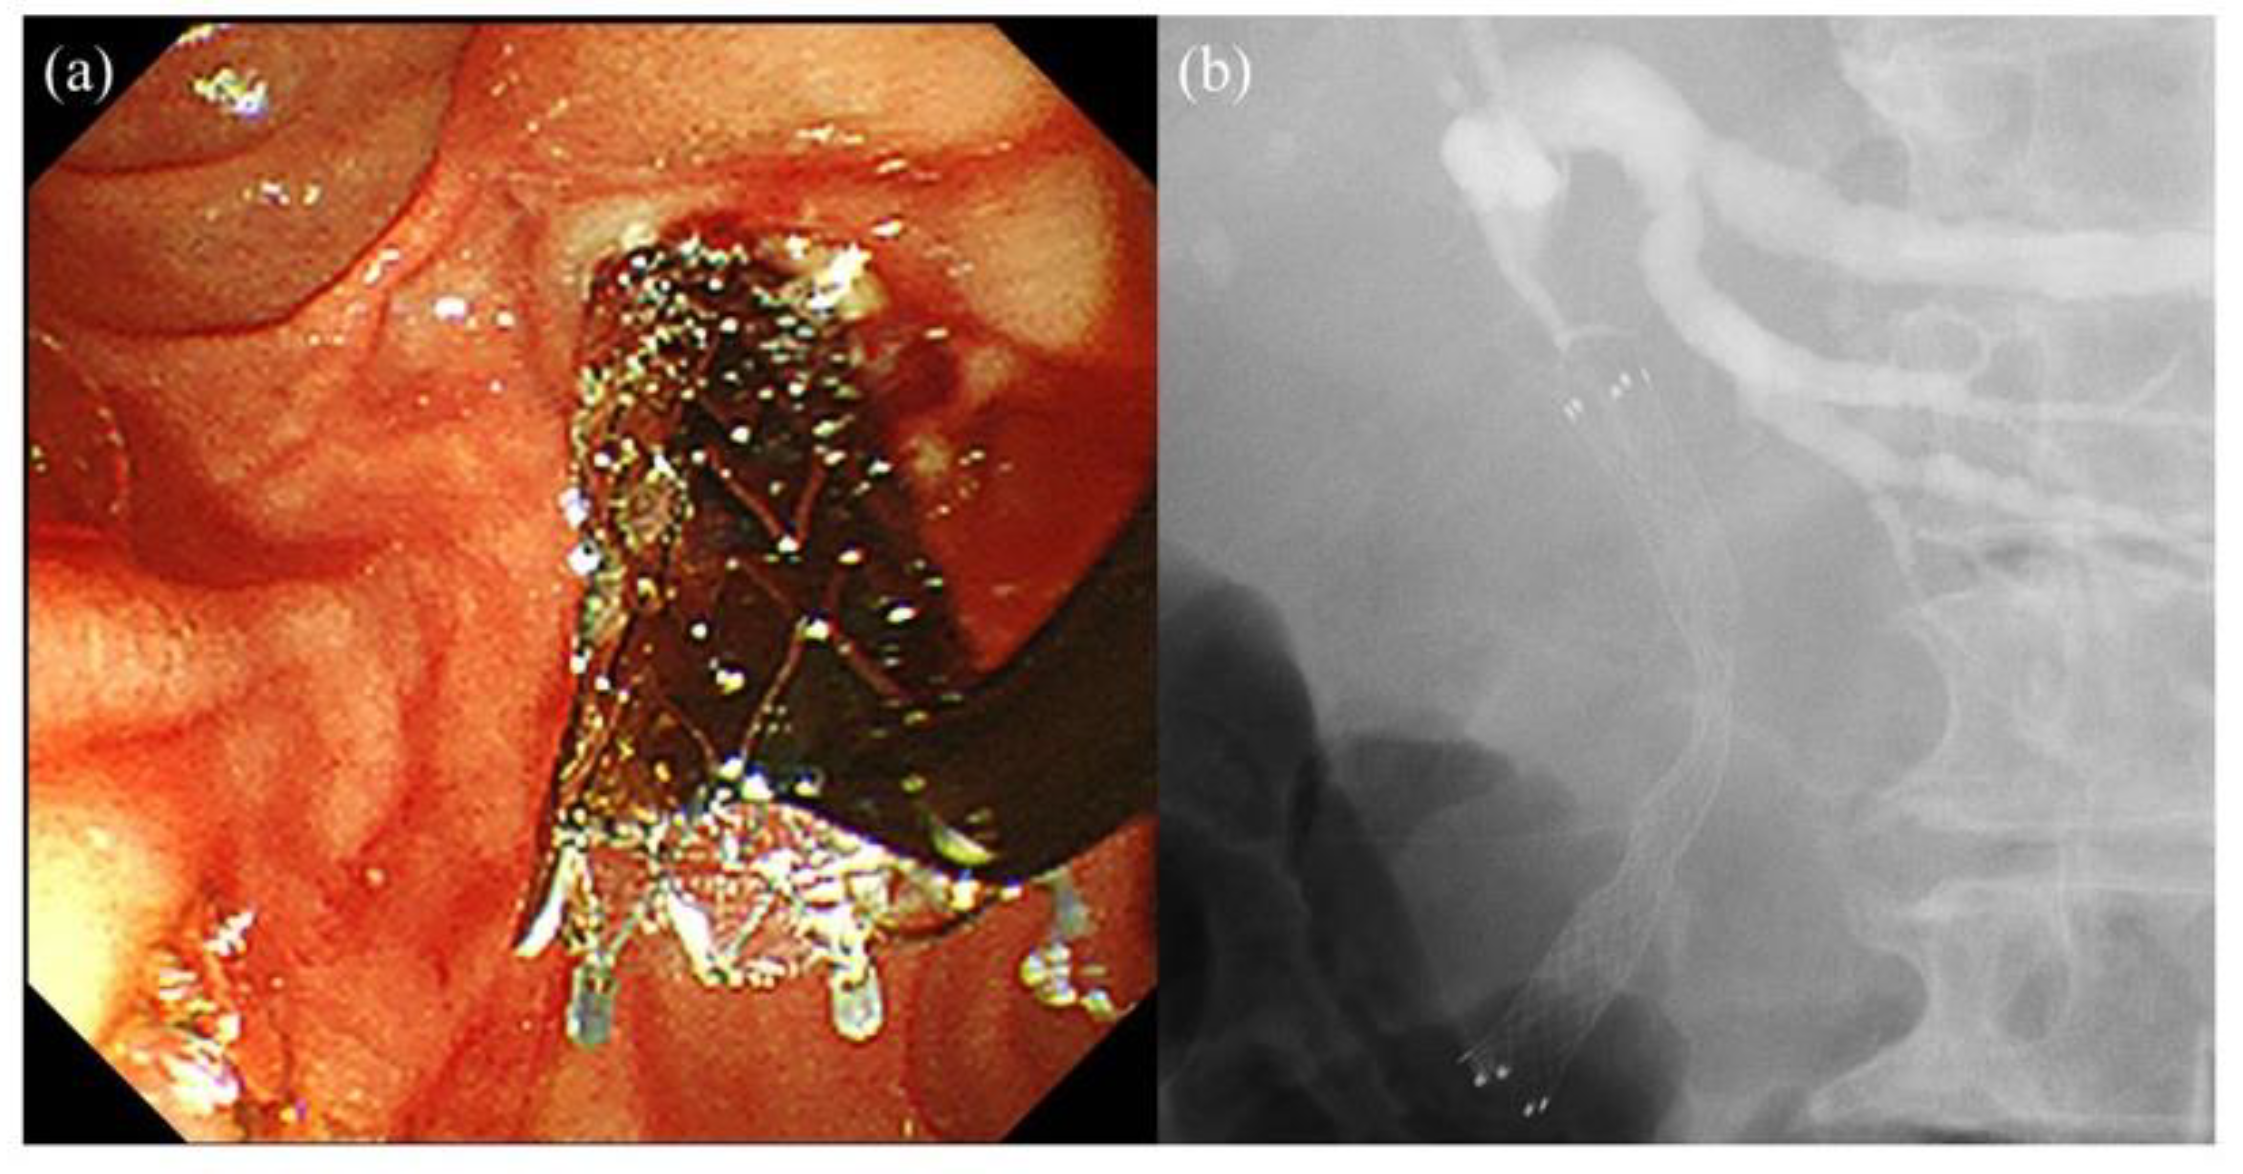

- Tanisaka, Y.; Ryozawa, S.; Kobayashi, M.; Harada, M.; Kobatake, T.; Omiya, K.; Iwano, H.; Arai, S.; Nonaka, K.; Mashimo, Y. Endoscopic removal of laser-cut covered self-expandable metallic biliary stents: A report of six cases. Mol. Clin. Oncol. 2018, 8, 269–273. [Google Scholar] [CrossRef]

- Marui, S.; Uza, N.; Yamazaki, H.; Ota, S.; Nakamura, T.; Yoshida, H.; Okada, H.; Hirano, T.; Kuwada, T.; Sogabe, Y.; et al. Utility of laser-cut covered self-expandable metal stents for unresectable malignant distal biliary obstruction: A single-center experience. Endoscopy 2020, 52, 664–668. [Google Scholar] [CrossRef]

- Tanisaka, Y.; Mizuide, M.; Fujita, A.; Ogawa, T.; Katsuda, H.; Saito, Y.; Ryozawa, S. Hemorrhage after laser-cut covered self-expandable metal stent removal. Endoscopy 2021. [Google Scholar] [CrossRef]

- Tanisaka, Y.; Mizuide, M.; Fujita, A.; Ogawa, T.; Katsuda, H.; Saito, Y.; Miyaguchi, K.; Araki, R.; Ryozawa, S. Can the laser-cut covered self-expandable metallic stent be the first choice for patients with unresectable distal malignant biliary obstruction? (with video). J. Hepatobiliary Pancreat. Sci. 2021. [Google Scholar] [CrossRef]